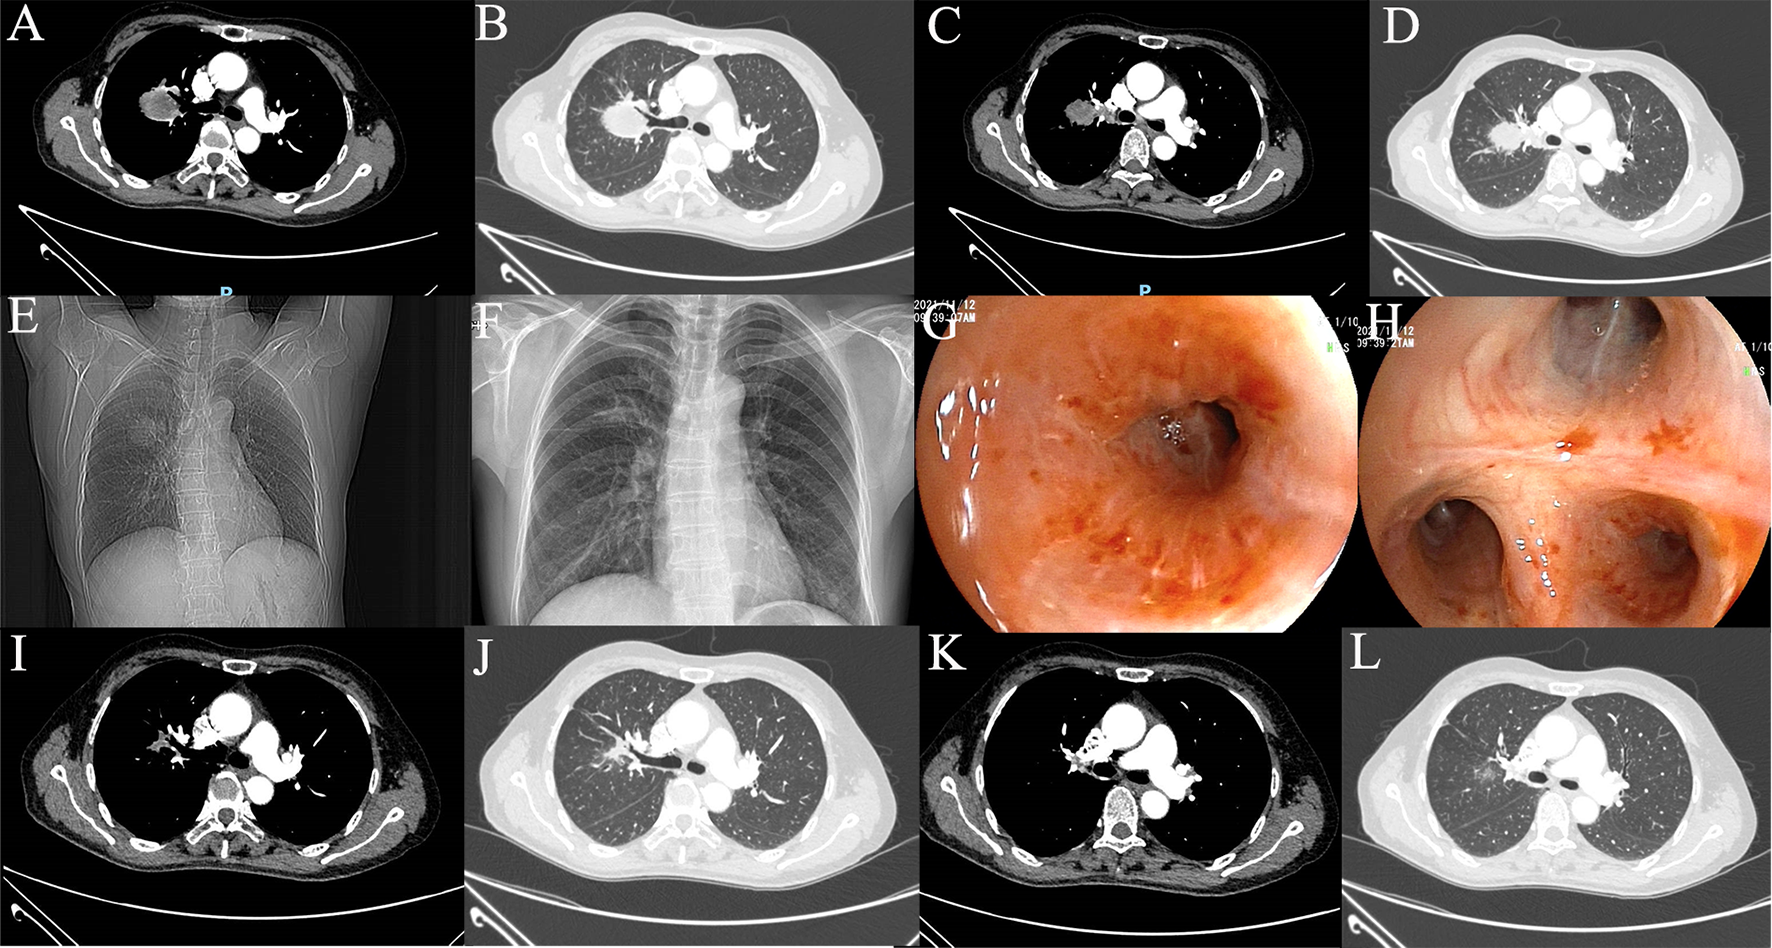

The 58-year-old patient was female and visited our hospital for one-month hemoptysis with no history of chronic diseases, smoking, and alcohol use (Figure 1). The X-ray and enhanced computed tomography (CT) demonstrated a mass in the upper lobe of the right lung (about 3.7 cm × 3.4 cm × 3.5 cm) with lobulated border and burrs, partially-occluded bronchial branches, and there were no obvious enlargement of mediastinal and bilateral hilar lymph nodes, and partial calcification. Central lung cancer was considered (Figures 2A–D). Carcinoembryonic antigen (CEA) was 86.98 ng/ml and the cytokeratin 19 fragment (CY21-1) was 4.06 ng/ml. Fiberoptic bronchoscopy indicated neoplasms in the posterior segment of the right upper lung, endoscopic biopsy suggested NSCLC (Figures 2G, H), and immunohistochemistry showed P40(+) and TTF-1 (–), suggestive of squamous cell carcinoma (Figures 3A, B). A few dyskaryotic cells were detected in bronchoalveolar lavage fluid (BALF). No significant metastasis was identified via upper abdominal enhanced CT scan, contrast-enhanced magnetic resonance imaging (MRI) of the head, and whole-body bone emission CT (ECT) scan. Taken together, the patient was classified as cT2aN0M0, stage IB. The patient’s tumor was closely related to the right upper pulmonary artery branch (Figure 2C), and the possibility of angioplasty during direct surgery was high, increasing the risk of surgery. There is also the possibility of conversion to thoracotomy, which would be more traumatic for the patient. Considering that the patient was a squamous carcinoma with a low possibility of having driver mutations, the multidisciplinary consultation recommended that neoadjuvant immune combination chemotherapy treatment should be performed first followed by surgery while waiting for NGS test and immunohistochemistry results. After signing the informed consent, the patient received anti-PD-1 therapy plus platinum-based neoadjuvant therapy (intravenous injection of 200 mg Pembrolizumab, 30 mg/m2 lobaplatin + 260 mg/m2 nab-paclitaxel, D1, q3w). The patient developed grade 2 myelosuppression during therapy, which was treated with an injection of polyethylene glycol recombinant human granulocyte colony-stimulating factor (rhG-CSF) with no grade 3-5 adverse events (AEs) observed. In the meantime, next-generation sequencing (NGS) and immunohistochemical(IHC) detected EGFR p.L858R mutations (abundance 72.2%), PD-L1 expression (TPS=80%, CPS(Combined Positive Score)=80), and tumor mutational burden (TMB, 5.03Mut/Mb), accompanied by EGFR copy-number amplification as well as multiple gene mutations, such as NKX2-1 and TP53. Considering the occurrence of EGFR mutation, the followed therapy was dilemma, which dependent on the outcome of the first treatment session as informed before. After one course of neoadjuvant immunochemotherpy, CEA and CY21-1 were 23.17 ng/ml and 2.43 ng/ml, respectively, significantly lower than the pre-treatment levels. In the meantime, chest digital radiography (DR) showed a reduction of the right upper lung occupancy (Figures 2E, F), implying partial radiographical response. So, the second cycle immunochemotherapy was perfomed as plan. Three weeks later, subsequent to the application of the second course of neoadjuvant therapy, a chest X-ray and enhanced CT scan were performed, indicating a marked reduction of the lesion in the right upper lung(about 1.9 cm × 1.4 cm) with partially bronchial stricture. At this point, CEA and CY21-1 were 3.06 ng/ml and 1.81 ng/ml respectively. Besides, positron emission tomography-computed tomography (PET-CT) illustrated an irregular patchy hyperdense shadow (2.76 cm × 2.18 cm × 1.59 cm) near the hilum of the right lung upper lobe and a mild increase in radioactivity uptake (maximum SUV = 2.57, mean SUV = 2.37), indicating that the tumor activity was remarkably suppressed (Figures 2I-L). Partial response (PR) was assessed according to the Response Evaluation Criteria in Solid Tumors (RECIST) version 1.1. In the fifth week after the neoadjuvant therapy, the single-port right upper thoracoscopic lobectomy + mediastinal lymph node dissection was successfully performed, during which the blood loss was approximately 50 ml. Postoperative pathology (Figures 3C, D)showed that the mass was 2.5 cm × 2 cm × 1.5 cm and that the fibrous tissue of the tumor bed exhibited hyperplasia with degeneration. Lymphocytes infiltrated the areas containing multinucleated giant cells and foam cells without residual disease; the bronchial mucosa manifested chronic inflammation without residualdisease. Efficacy assessment of neoadjuvant therapy showed that pCR was achieved. The lymph nodes of 2R (0/2), 3A (0/2), 4R (0/1), group 7 (0/1), group 10 (0/1), group 11 (0/7), and group 12 (0/1) were disease-free. The bronchial stump of the right upper lung was also free of cancer cells. The patient recovered well and was discharged without any operation-related complications. Biopsy tissues and surgical samples were examined using multiplex immunohistochemistry (mIHC) to reveal the alterations of the tumor microenvironment (TME) after the application of neoadjuvant therapy, especially the inflammatory and immune cells. mIHC of biopsy tissues (Figures 3E, F) illustrated intratumoral presence of CD8+ T cells (111/mm2), and high infiltration of FoxP3 (244/mm2) and CD68 + CD163 + M2 macrophages (139/mm2). In the surgical samples (Figures 3G, H), large amounts of CD8+ T cells (511/mm2) and tertiary lymphoid structures were observed, while the number of CD68 + CD163 + M2 macrophages (32/mm2) and FoxP3+ (60/mm2) were substantially decreased. No genetic mutation was detected in the ctDNA of peripheral blood at the fourth postoperative week. The patient started receiving two cycles of adjuvant immuno-chemotherapy (intravenous injection of 200 mg Pembrolizumab, 30 mg/m2 lobaplatin + 260 mg/m2 nab-paclitaxel, D1, q3w) at the fifth week after surgery. The patient was in good physical condition at the 5-month follow-up visit and refused to accept the one-year single-agent immunotherapy due to financial factors.

Figure 2

Imaging examination. (A–D) Preoperative CT scan; (E) Preoperative DR image; (F) DR image after one cycle of neoadjuvant therapy; (G, H) Preoperative fiberoptic bronchoscopy image; (I–L) CT image after 2 cycles of neoadjuvant therapy.